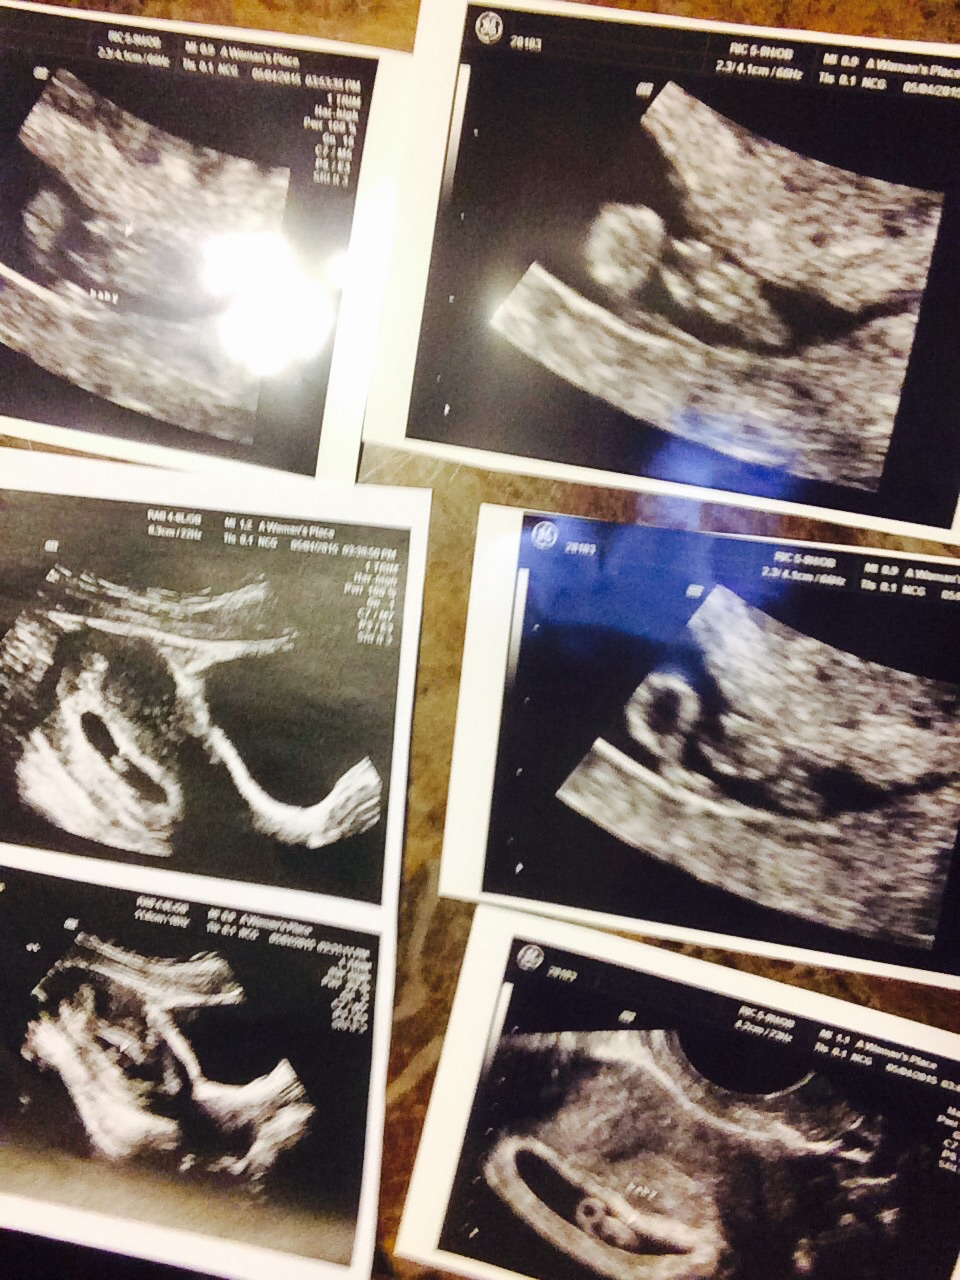

10w1d they zoomed in so I could see baby better, love my little human.. Still think the best was when my cousin goes congratulations your having a human